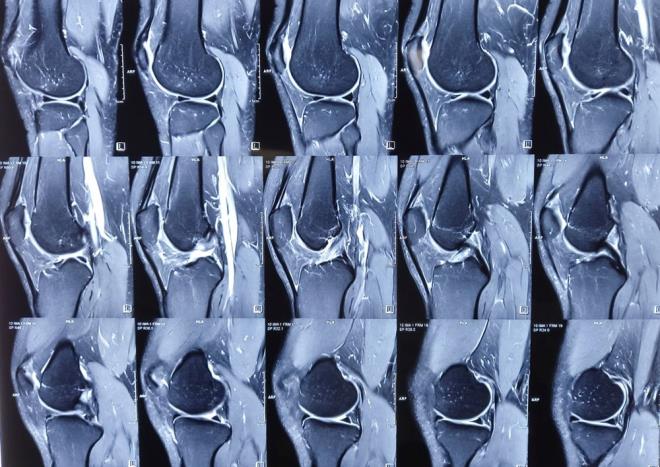

6. ARAŞTIRMA NASIL YAPILDI?    Lancet Oncology adlı bilimsel dergide yazan araştırmacılar, 170 hastanın taramalarında çıplak gözle görülemeyen retroperitoneal sarkom (karnın arka kısmındaki bağ dokusunda gelişen) belirtilerini tespit etmek için radyomiks adı verilen bir teknik kullandı.

ARAŞTIRMA NASIL YAPILDI? Lancet Oncology adlı bilimsel dergide yazan araştırmacılar, 170 hastanın taramalarında çıplak gözle görülemeyen retroperitoneal sarkom (karnın arka kısmındaki bağ dokusunda gelişen) belirtilerini tespit etmek için radyomiks adı verilen bir teknik kullandı.

7. Yapay zeka algoritması bu verilerle, Avrupa ve ABD'deki diğer 89 hastanın tümörlerinin agresifliğini, kanserli dokunun küçük bir kısmının mikroskop altında analiz edildiği biyopsilerden çok daha doğru bir şekilde röntgen görüntülerini inceleyerek değerlendirdi.

Yapay zeka algoritması bu verilerle, Avrupa ve ABD'deki diğer 89 hastanın tümörlerinin agresifliğini, kanserli dokunun küçük bir kısmının mikroskop altında analiz edildiği biyopsilerden çok daha doğru bir şekilde röntgen görüntülerini inceleyerek değerlendirdi.